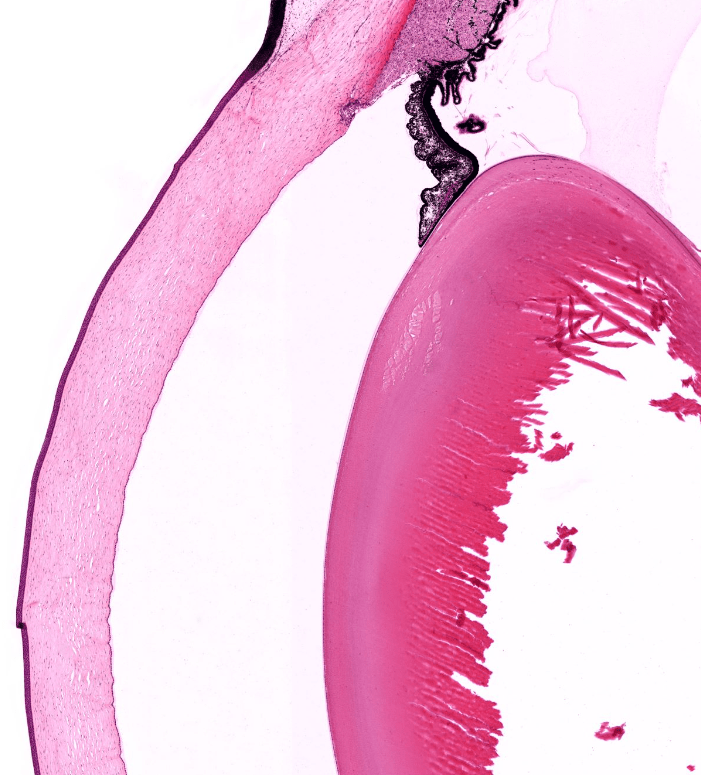

IRIS

CUERPO CILIAR

CRISTALINO